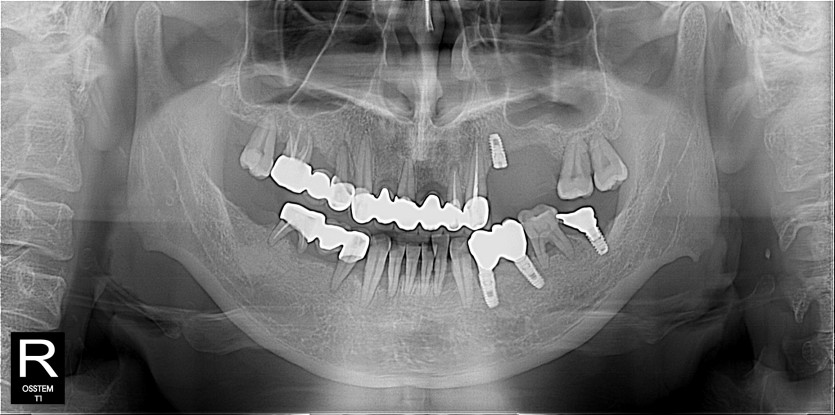

임플란트 사례